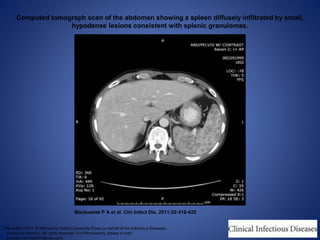

Computed tomograph scan of the abdomen showing a spleen diffusely infiltrated by small,

hypodense lesions consistent with splenic granulomas.

Mackowiak P A et al. Clin Infect Dis. 2011;52:418-420